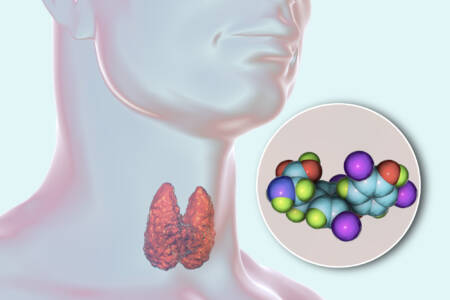

A tireoidite de Hashimoto é uma condição autoimune que atinge a glândula tireoide, localizada na parte frontal do pescoço. O sistema imunológico, por engano, passa a atacar essa glândula, comprometendo sua função e levando, na maioria dos casos, ao hipotireoidismo – uma condição marcada pela baixa produção dos hormônios tireoidianos.

Essa doença afeta principalmente mulheres entre 30 e 50 anos, mas pode acometer pessoas de qualquer idade e gênero. É uma das causas mais comuns de hipotireoidismo no mundo, e muitas vezes se desenvolve de forma silenciosa.

Exames de sangue que medem os níveis de TSH, T3 e T4, além da presença de anticorpos anti-TPO e anti-tireoglobulina, são essenciais para confirmar o diagnóstico. Quanto mais cedo for identificada, maiores são as chances de controlar os sintomas e manter a qualidade de vida do paciente.

O tratamento normalmente envolve o uso diário de levotiroxina, um hormônio sintético que substitui a função da tireoide. Acompanhamento médico regular é fundamental para ajustar a dose e monitorar a evolução da doença.